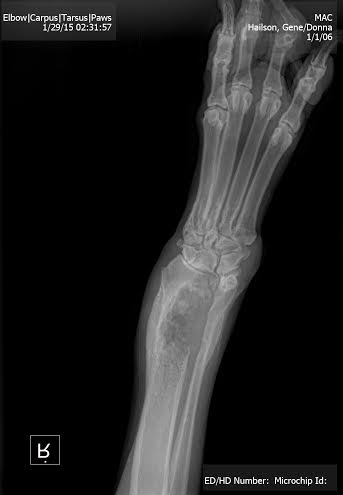

While on the road, Gene and I sometimes plant ourselves in a RV park central to an area we want to explore. When we’re in that mode, we do our exploring and then move on to another place often after just a few days. We have also, as I mentioned earlier on, enjoyed the occasional seasonal work camping. We were on such an assignment in Big Cypress, Florida, when we began to notice a change in Mac. He started to limp and, when Gene shaved him and Molly down so they might better acclimate to the heat and humidity of the swamp, we noticed a protuberance on the elbow of his right leg. An x-ray subsequently revealed that Mac had contracted a cancer, Osteosarcoma. Our veterinarian, John Morton, of the Golden Gate Animal Clinic in Naples, showed us copies of the film and it was clear to see where the bone had been eaten away by the disease.